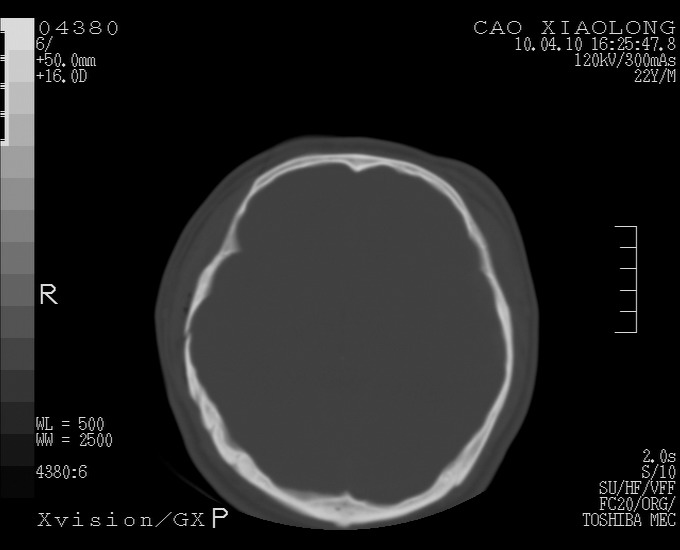

以下是引用随光逐影在2010-4-11 11:00:00的发言:[br]1)左侧额颞顶部硬膜下血肿。2)蛛网膜下腔出血。3)右侧颞顶部颅骨线形骨折。[br][br]20小时后复查:左侧额颞叶脑挫裂伤;左侧额颞顶部硬膜下血肿及蛛网膜下腔出血有吸收表现;右侧颞顶部颅骨线形骨折。[br]